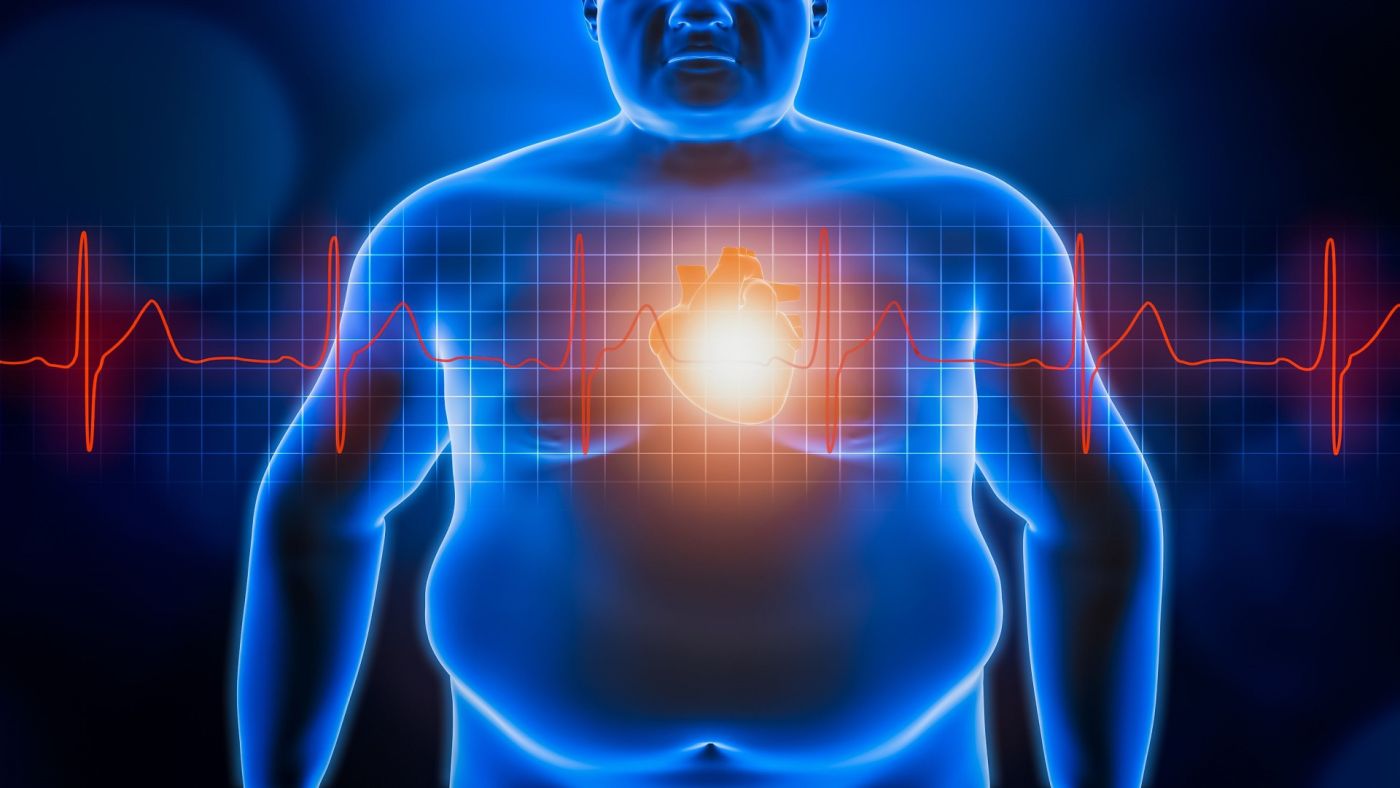

Όταν ακούτε τη λέξη «παχυσαρκία», ποιο είναι το πρώτο πράγμα που σκέφτεστε;

Το πιθανότερο είναι κάτι που δεν θα ανταποκρίνεται στην πραγματικότητα, καθώς η πλειονότητα εξ ημών πιστεύει ότι είναι απόρροια της λαιμαργίας και της αδιαφορίας για την υγεία.

Η πραγματικότητα όμως δεν θα μπορούσε να είναι πιο διαφορετική από αυτό.

«Η παχυσαρκία είναι μία ασθένεια, κατά την οποία η παθολογική συσσώρευση σωματικού λίπους προκαλεί προβλήματα υγείας», λέει η Dr. Leslie Heinberg, καθηγήτρια Ψυχιατρικής στο Πανεπιστήμιο Case Western Reserve, στο Οχάιο.

«Η πιο συχνή λανθασμένη αντίληψη γι’ αυτήν είναι ότι αποτελεί διαταραχή του τρόπου ζωής. Ότι δηλαδή οι πάσχοντες παχαίνουν λόγω κακής διατροφής ή καθιστικής ζωής. Η παχυσαρκία είναι πολύ πιο πολύπλοκη από αυτό και οφείλεται σε συνδυασμό πολλών παραγόντων».

Ήδη από τα μέσα της δεκαετίας του 2010, ο Παγκόσμιος Οργανισμός Υγείας (WHO) και η Αμερικανική Ιατρική Εταιρεία (ΑΜΑ) την έχουν αναγνωρίσει επισήμως ως χρόνια νόσο. Τονίζουν επίσης ότι προκαλεί πολλές λειτουργικές αλλαγές που απαιτούν συνδυασμό θεραπειών και προληπτικών παρεμβάσεων.

Ο ΔΜΣ και το σωματικό λίπος

Η παχυσαρκία είθισται να αξιολογείται με τον δείκτη μάζας σώματος (ΔΜΣ). Ο δείκτης αυτός υπολογίζεται πολύ εύκολα. Δεν έχετε παρά να διαιρέσετε το βάρος σας (σε κιλά) με το τετράγωνο του ύψους σας (σε μέτρα). Αν λ.χ. ζυγίζετε 75 κιλά και έχετε ύψος 1,65 μέτρα, κάνετε τη διαίρεση 75 διά 2,7225 (προκύπτει από το 1,65 επί 1,65).

Όταν το αποτέλεσμα της διαίρεσης (πηλίκο) είναι πάνω από 30, σημαίνει ότι είστε παχύσαρκοι. Αν είναι πάνω από 40, σημαίνει ότι έχετε νοσογόνο (ή κακοήθη) παχυσαρκία. Φυσιολογικές είναι οι τιμές του κάτω από 18,5 έως 24,9. Τέλος, οι τιμές από 25 έως 29,9 σημαίνουν υπέρβαρο άτομο.

Ωστόσο, πιο σημαντικό από τον ΔΜΣ είναι:

- Το ποσοστό του σωματικού λίπους έναντι της μυϊκής μάζας στο σώμα σας

- Τα σημεία όπου συσσωρεύεται το σωματικό λίπος

«Η συσσώρευση στην κοιλιά (κοιλιακή παχυσαρκία) είναι η πιο επικίνδυνη απ’ όλες», τονίζει η Dr. Heinberg, η οποία είναι επίσης διευθύντρια του Τμήματος Συμπεριφορικής Ιατρικής στο Βαριατρικό & Μεταβολικό Ινστιτούτο της Cleveland Clinic.